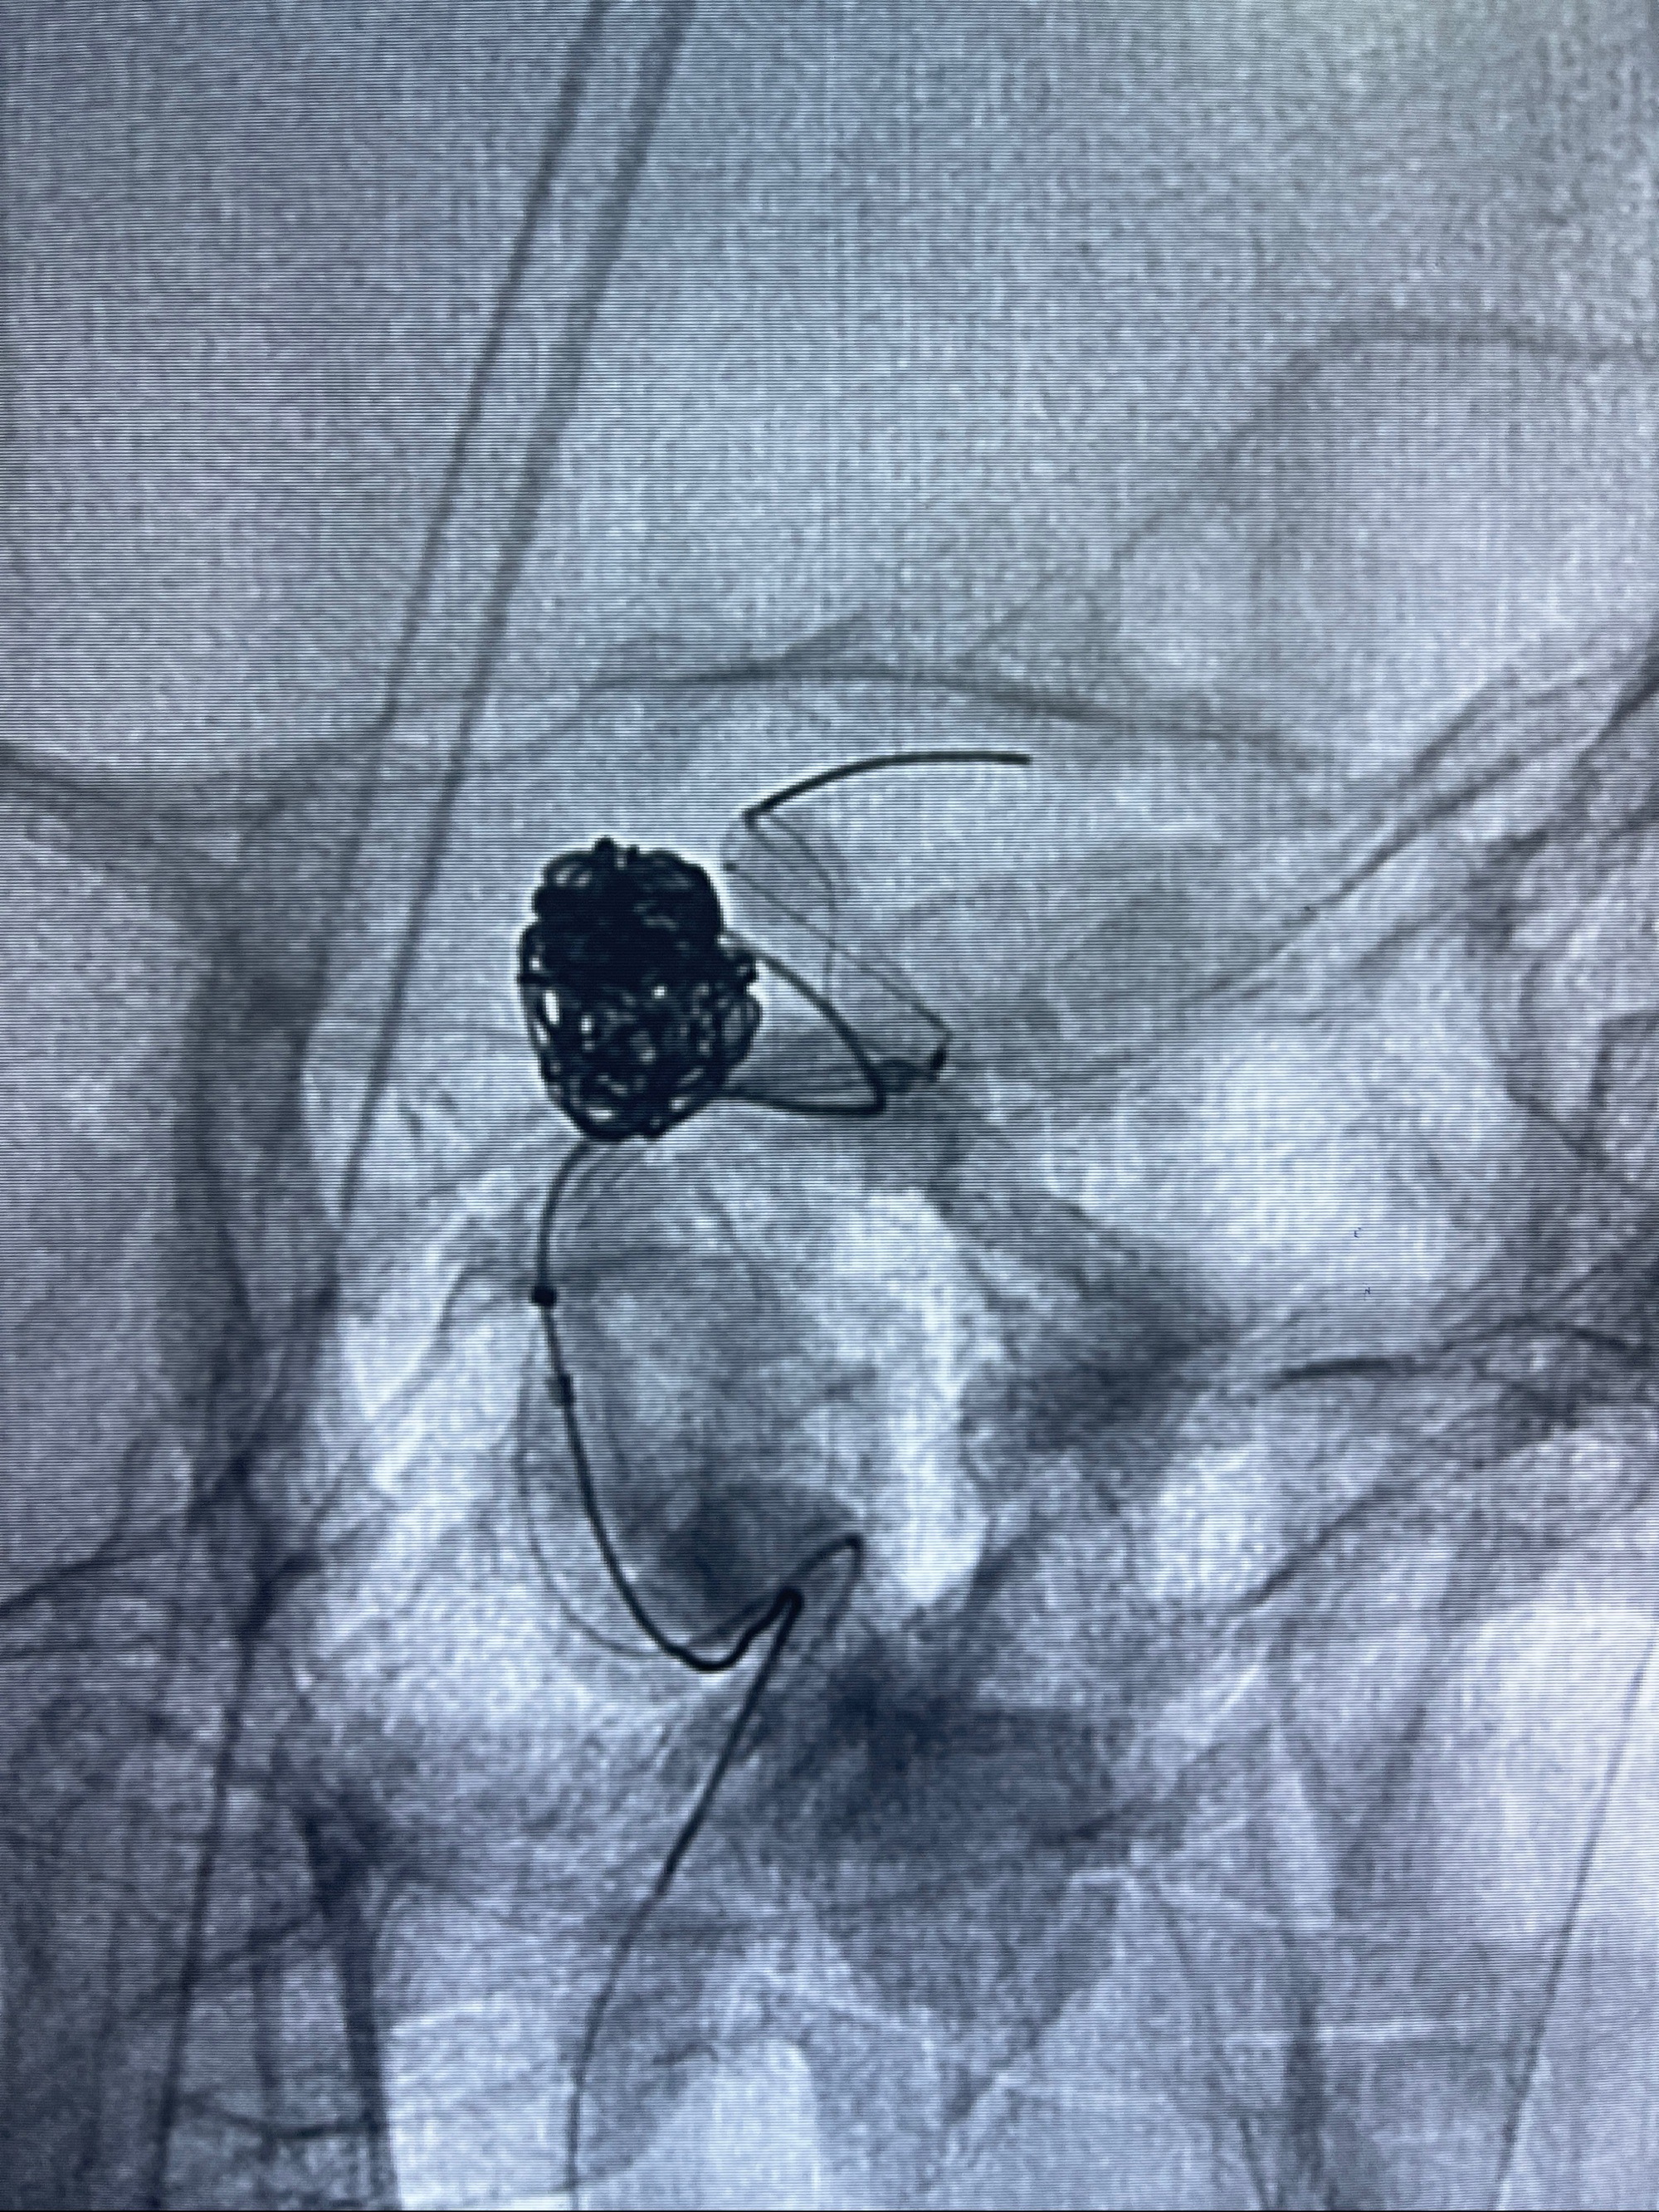

2023-08-30DSA:左侧颈内动脉眼动脉动脉瘤,约3*9.2*7.3mm大小

密网支架辅助栓塞

- Tubridge 4.0-20mm密网支架

- 加奇微弹簧圈:7*30/6*20/5*20/2*8

术后3D显示支架贴壁佳